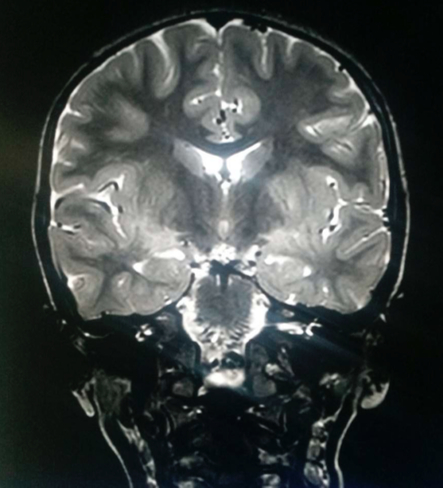

di Emergenza e Accettazione, dove viene riscontrata una leucocitosi neutrofila (26.440/mm3, neutrofili 88,9%) e una adenomesenterite all’ecografia, per cui dopo breve osservazione viene dimessa. Dopo un mese alla sintomatologia si aggiunge febbre (38,5 °C), deviazione del collo, astenia agli arti inferiori e deambulazione incerta, per cui si ricovera. È sofferente, irritabile e presenta rigidità nucale con posizione preferenziale supina. Nel sospetto di meningoencefalite viene eseguita una RMN cranio-encefalo-rachide, che mostra un’alterazione di segnale a carattere flogistico/edemigeno corticale e sottocorticale in sede parietale, caudale occipitale e temporale omolaterale con enhancement leptomeningeo e analoga alterazione dei talami (Figure 1 e 2).

Alla RM encefalo si evidenzia una alterazione a margini sfumati senza enhacement a livello di nuclei dentati, porzione posteriore del ponte, nuclei subtalamici, talamo anteriore, teste dei nuclei caudati, ginocchio del corpo calloso, insule, della regione temporo-mesiale bilaterale, frontale, parietale posteriore e dei centri semiovali. I reperti coinvolgenti la sostanza bianca sottocorticale e i gangli della base in modo asimmetrico sono compatibili con riacutizzazione di processo infiammatorio (ADEM), per cui si imposta terapia con metilprednisolone (30 mg/kg in bolo) per 4 giorni seguito da prednisone per os con riduzione graduale in 4 settimane. La bambina presenta rapida risposta clinica e normalizzazione dell’EO e dell’EEG. Viene dimessa affidandola alla Neurologia per evidenziare una eventuale disseminazione spaziale-temporale delle lesioni, che sarebbe compatibile con una sclerosi multipla a esordio pediatrico.